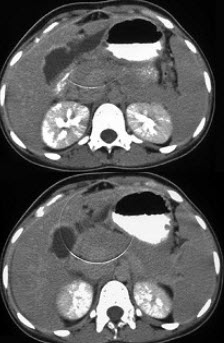

女,45岁,急性右上腹剧痛2小时,向右肩放射,影像检查如图,应诊断为( )

A:急性胆囊炎

B:慢性胆囊炎

C:胆囊穿孔

D:胆囊腺肌增生症

E:胆道梗阻